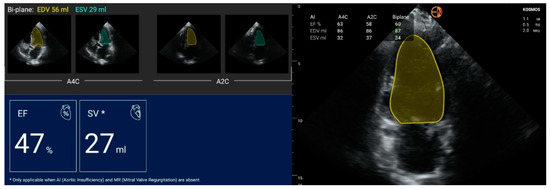

| FEVS (%) | mean (stdev) | 51.4 (9.1) | 51.7 (9.8) | −0.33 (4.96) | −0.3 [−10.1 to 9.4] |

| median [Q1 to Q3] | 53.5 [46 to 57] | 52.5 [48 to 58.5] | −1 [−3 to 4] | ||

| {min to max} | {30 to 67} | {26 to 68} | {−11 to 10} |